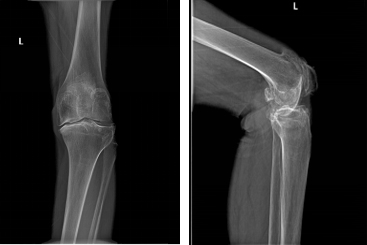

患者邱某,女,75岁,因反复左膝关节疼痛10余年入院,患者10余年前无明显诱因出现左膝关节疼痛,上下楼梯明显,未予重视,未行系统治疗,左膝关节疼痛逐步加重,左膝关节内翻畸形,行走约100米出现疼痛加重需休息,日常生活自理困难。

术前X片: